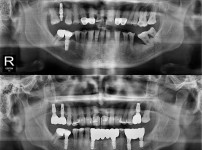

全口种植牙